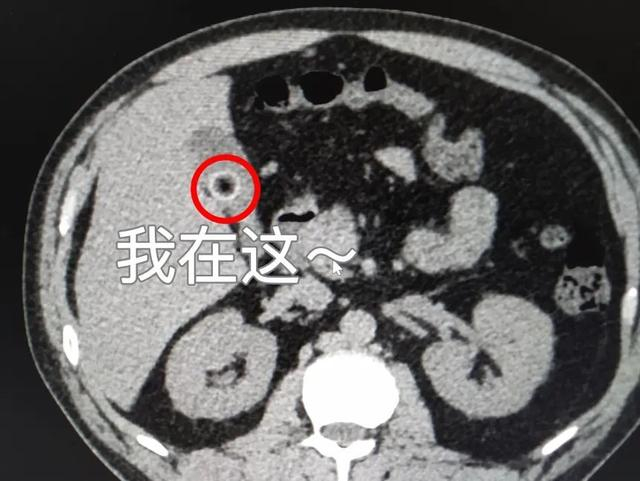

混合型结石

(CT表现上为高低混杂密度)CT表现为边缘呈环状高密度,中心为低密度区充盈缺损。